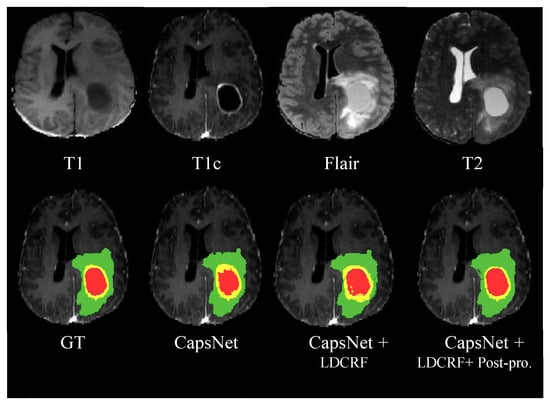

| Methods | Dice | Sensitivity | Specificity | ||||||

|---|---|---|---|---|---|---|---|---|---|

| Complete | Core | Enhancing | Complete | Core | Enhancing | Complete | Core | Enhancing | |

| CapsNet | 0.83 | 0.81 | 0.80 | 0.80 | 0.77 | 0.78 | 0.87 | 0.85 | 0.82 |

| CapsNet + LDCRF | 0.87 | 0.85 | 0.83 | 0.85 | 0.83 | 0.81 | 0.88 | 0.86 | 0.84 |

| CapsNet + LDCRF + Post-procesing | 0.92 | 0.88 | 0.85 | 0.90 | 0.86 | 0.85 | 0.93 | 0.91 | 0.87 |